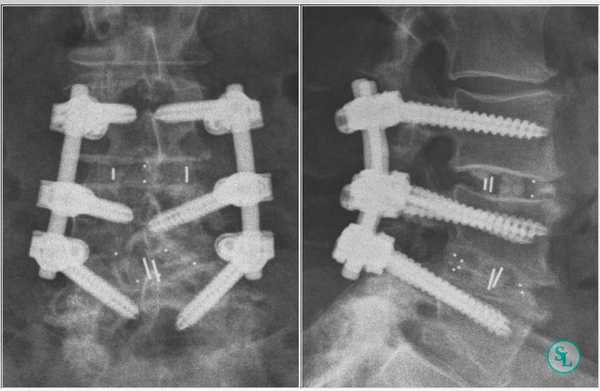

Индексы ASDAS, по-видимому, лучше, чем BASDAI, в связи с более строгой валидностью и высокой дискриминантной способностью. Индексы ASDAS «работают» при АС, ранних формах спондилоартропатий, рентгенонегативном осевом и периферическом АС. С помощью индексов ASAS определяются неактивная болезнь, умеренная, высокая и очень высокая активность заболевания при соответствующих им значениях индексов ASDAS (1,3, 2,1 и 3,5 единицы). Интервал изменения ≥ 1,1 единицы соответствует клинически значимому улучшению, а интервал ≥ 2,0 единиц — значительному улучшению [4]. По мнению экспертов, ASDAS не более 2,1 является целью лечения Т2Т [5]. Нами ниже предложен алгоритм лечения аксиального АС (рис. 1). Однако данные строгих клинических испытаний, способных доказать данную концепцию, пока отсутствуют. Актуальность этих поисков демонстрируют результаты неуклонного прогрессирования болезни, требующего хирургического вмешательства, которые представлены на рисунках 2 и 3.